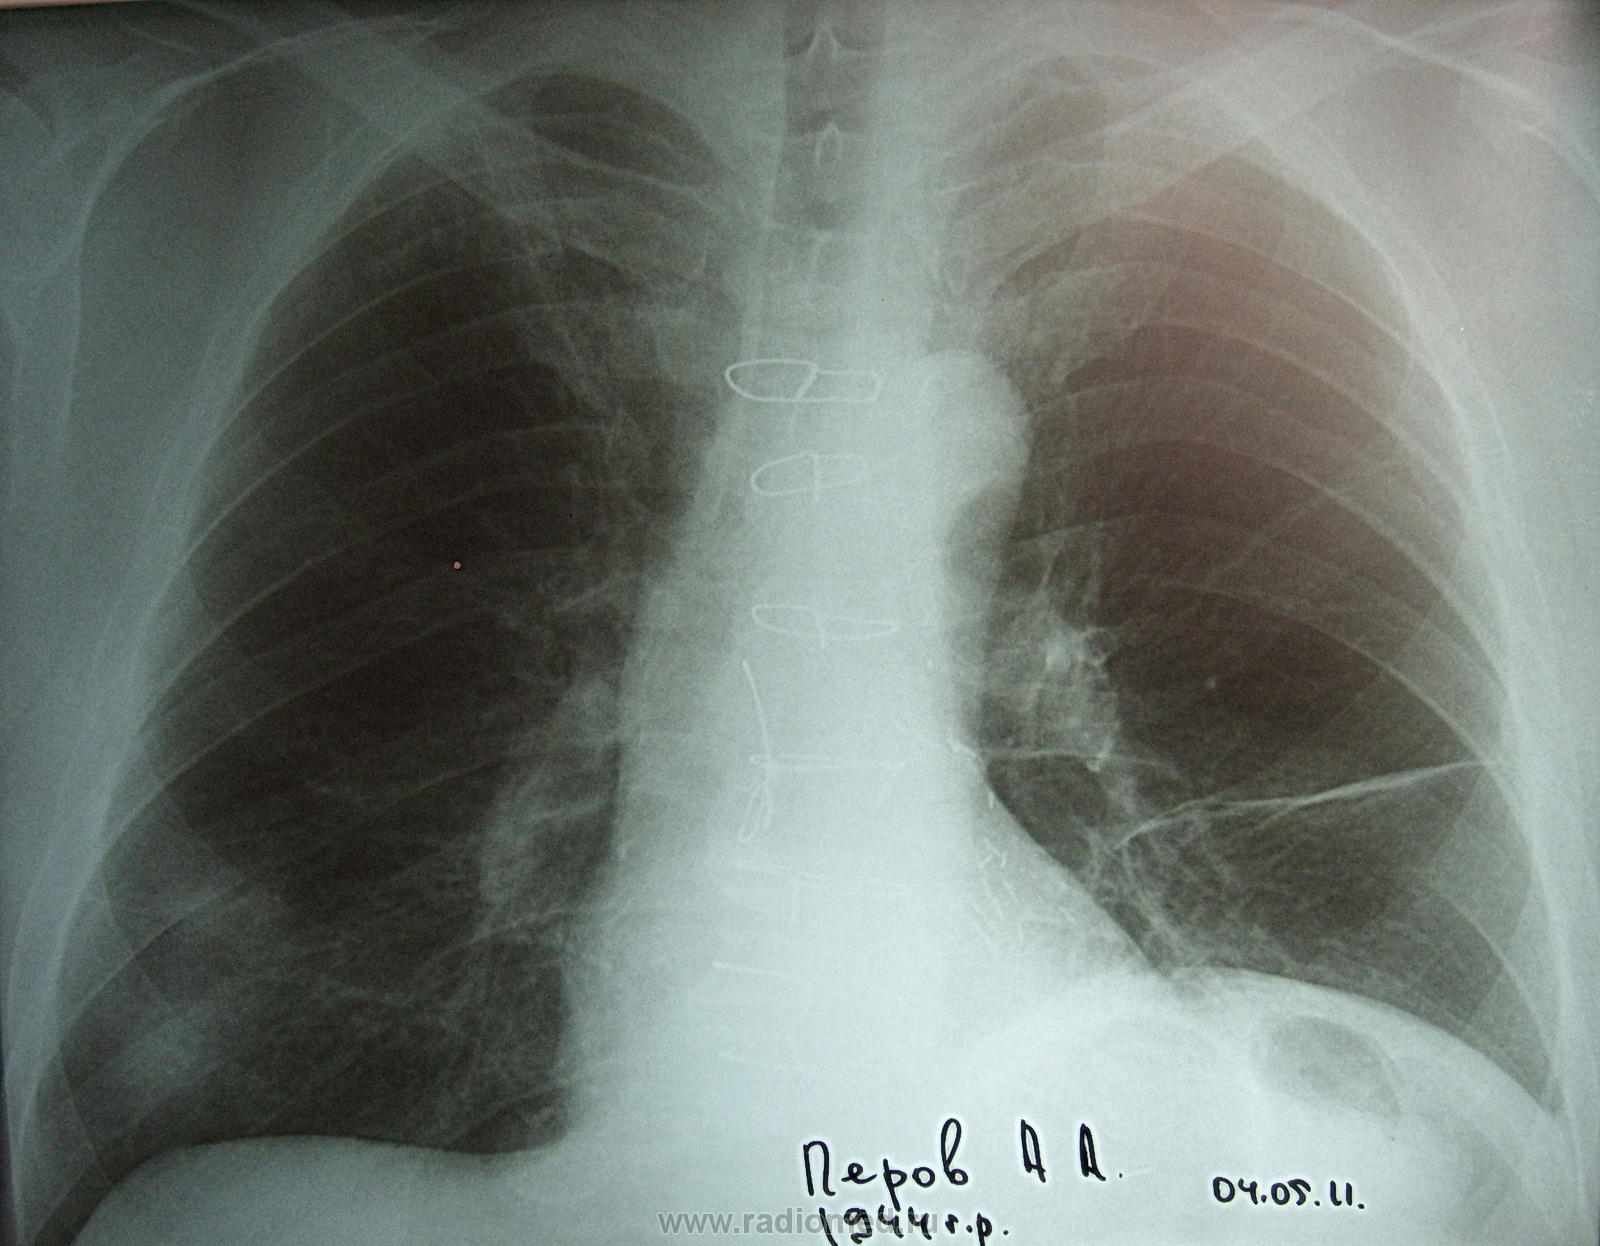

Мужчина 1944 года рождения обратился с жалобами по поводу сухого кашля, который около месяца его беспокоит. Температуры нет, аускультативно терапевт выслушывает хрипы. В прошлом была операция по поводу шунтирования. Давно, в молодости был консультирован у фтизиатра. который снял все подозрения, связанные с очаговыми включениями справа в в\доле.

Иигибиторы апф? А нижняя доля справа, а м/долевая плевра слева?

Справа в н отделе (проекция S 9) - инфильтрация ? На боковом какая-то подозрительно ровная треугольная тень рисуется в этих отделах (шварта?)

может,полечим банальную пневмонию справа?она же, вероятно, и дает тень на боковом.

С учетом операции... я бы в первую очередь подумала об инфаркной пневмонии с затянувшимся течением. Сегментарная, S9 справа. И рекомендовала бы контроль после противовоспалительного лечения. При отсутствии динамики - линейная или компьютерная томография. И, разумеется, поднять архив.

Слева высокое стояние купола диафрагмы, может, только за счет раздутого газом селезеночного угла, да только толщина диафрагмы слева не позволяет полностью исключить наддиафрагмальный выпот... Много вопросов, нужен ФЛГ-архив.

лёгком определяется дисковидный ателектаз. У меня возник вопрос по поводу ретростернального пространства, в боковой проекции,  есть ли там воздух? Мне показалось что есть.

Справа я вижу два фокуса воспалительных в н/д, фиброз в с/д.

Слева купол поднят из-за кишки раздутой? И дисковидный ателектаз из-за неё же? Спаек-то не видно, и плеврального выпота не вижу.

Острого не вижу.Эмфизема, участки пневмосклероза(не исключаются перенесенные инфарктные пневмонии).Двусторонний деформирующий бронхит.